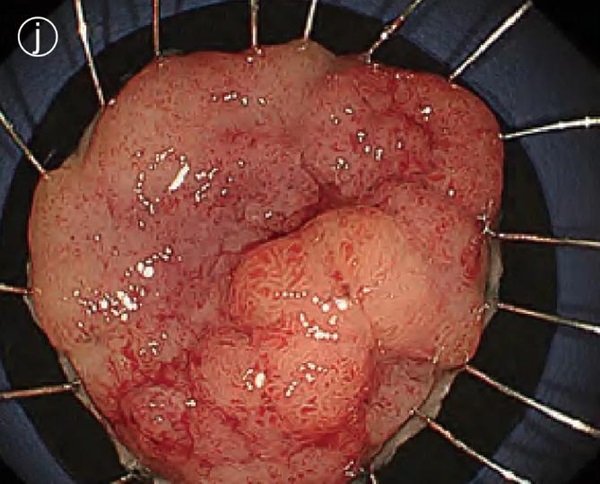

j. Specimen fixation

The excised specimen was attached to a rubber sheet.

Final pathological diagnosis: intramucosal carcinoma (Tis)